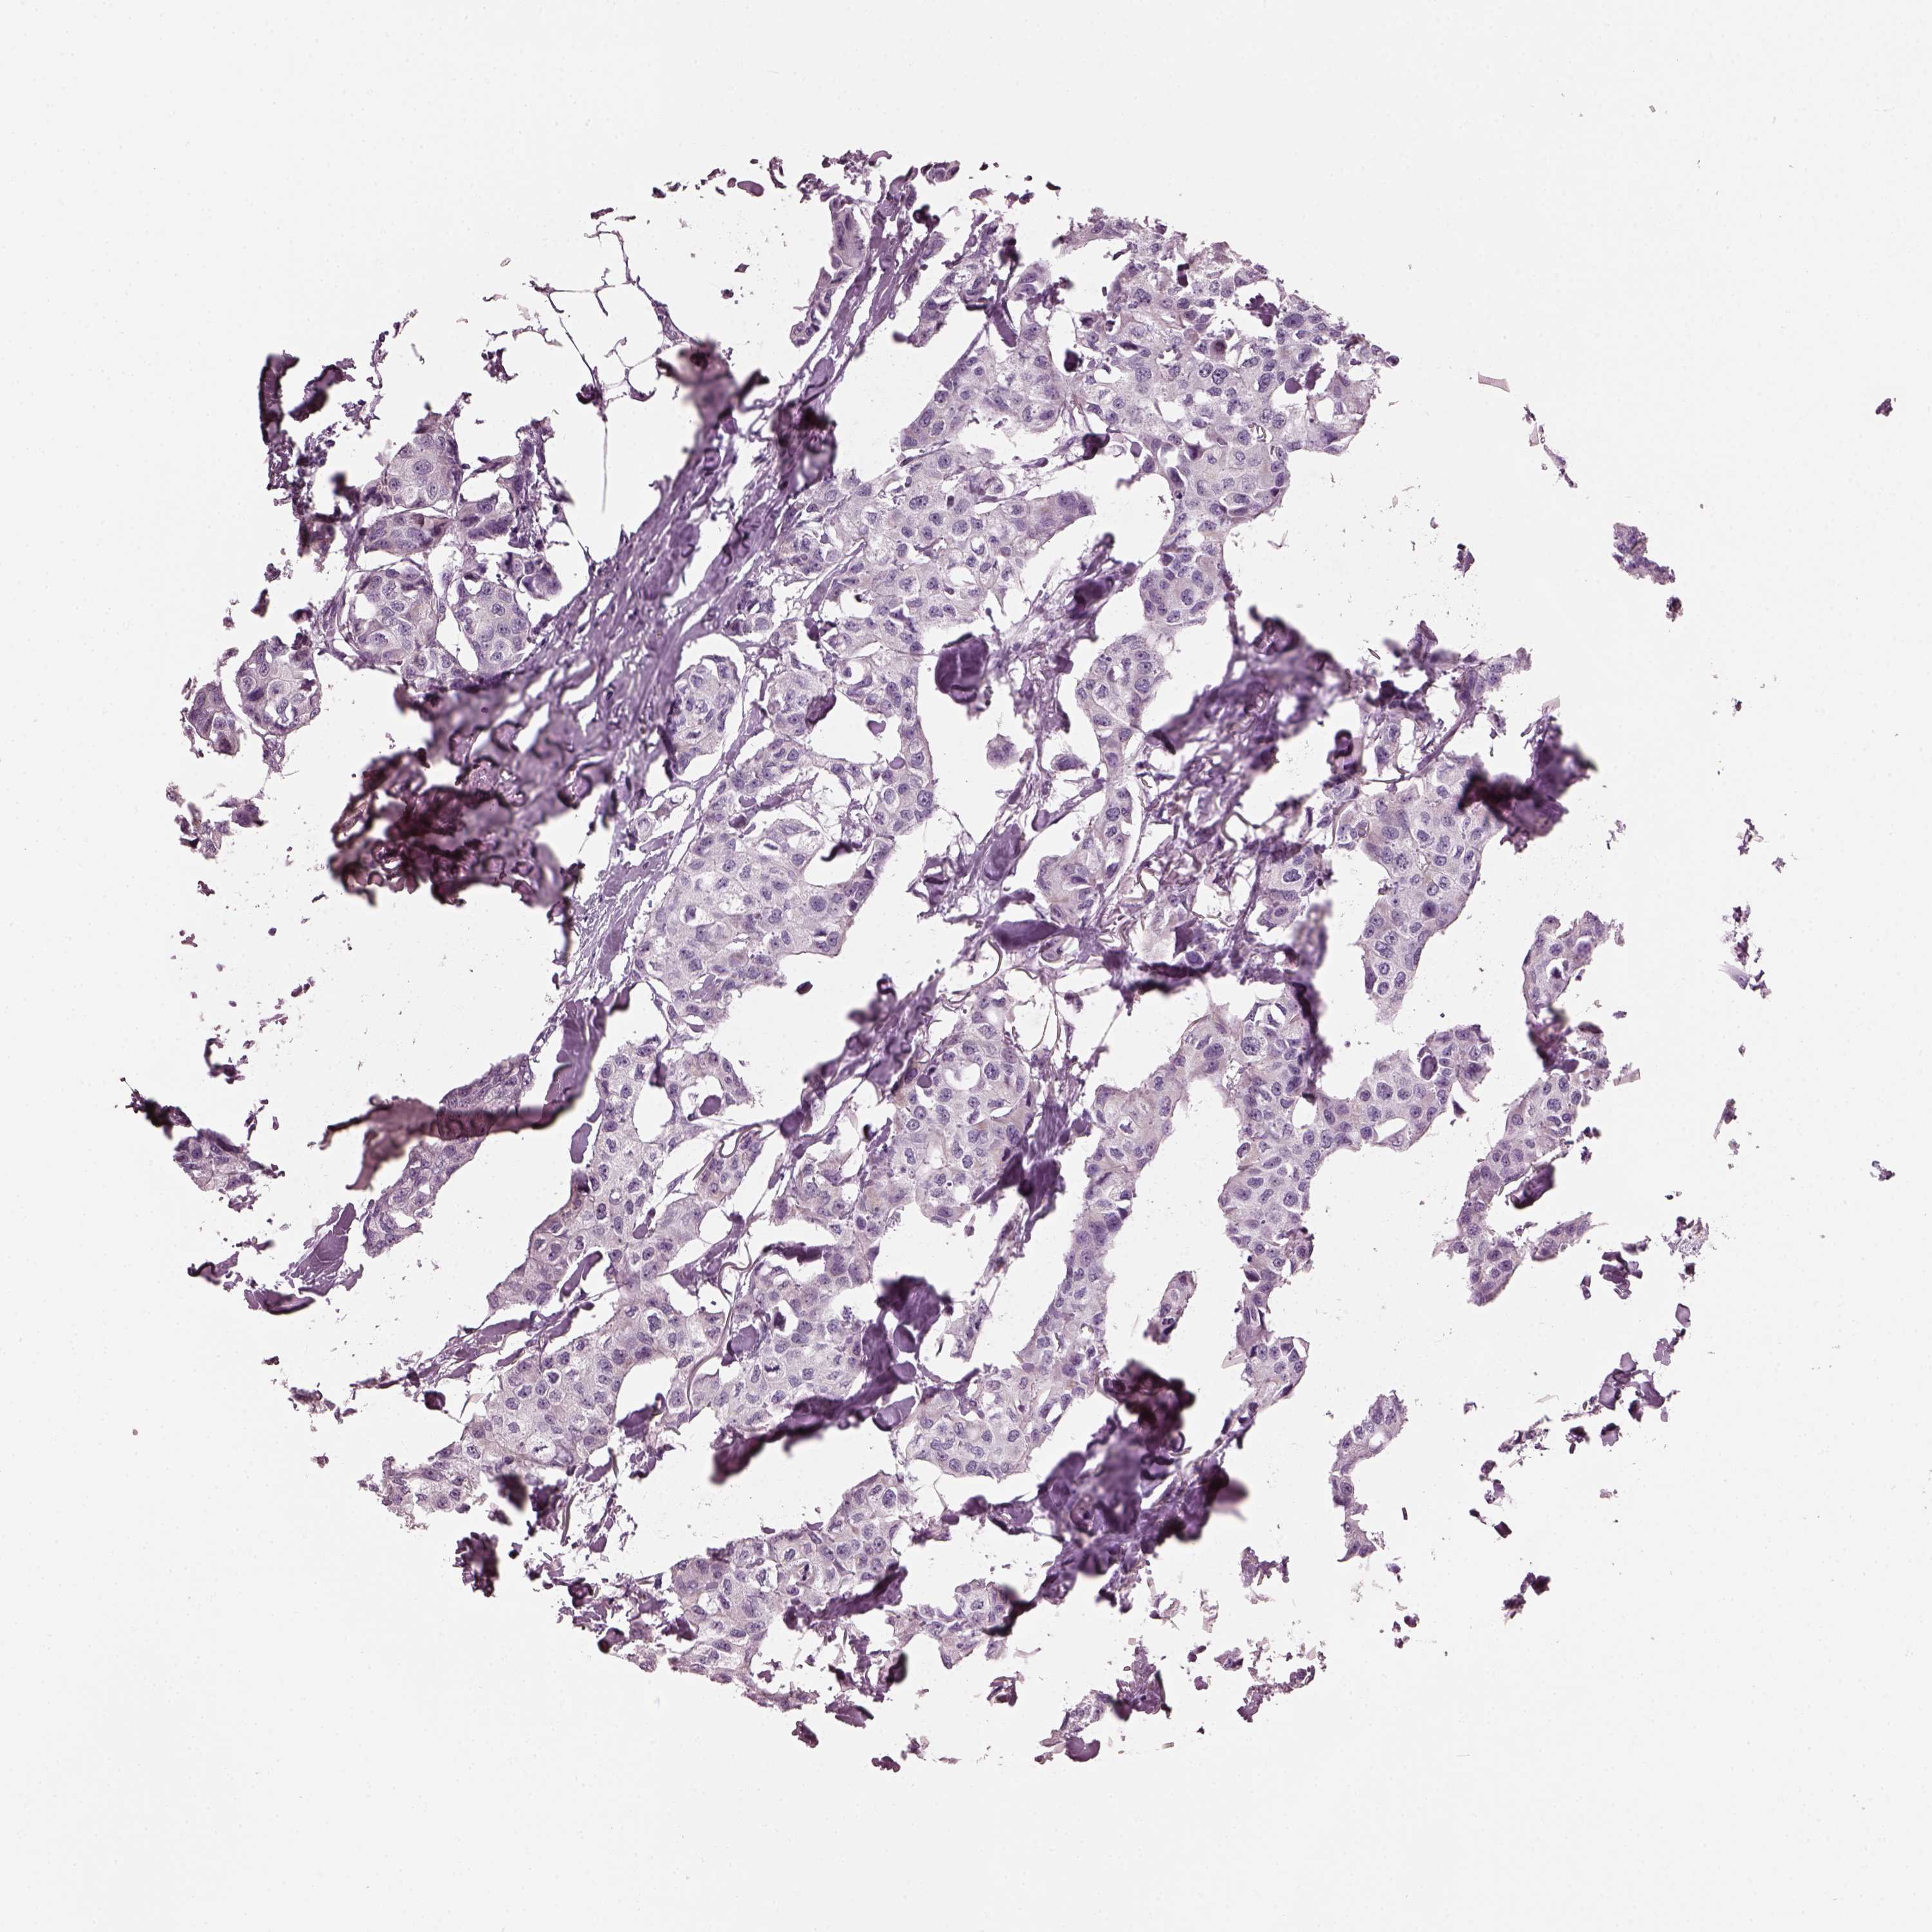

Breast cancer

Human cancer